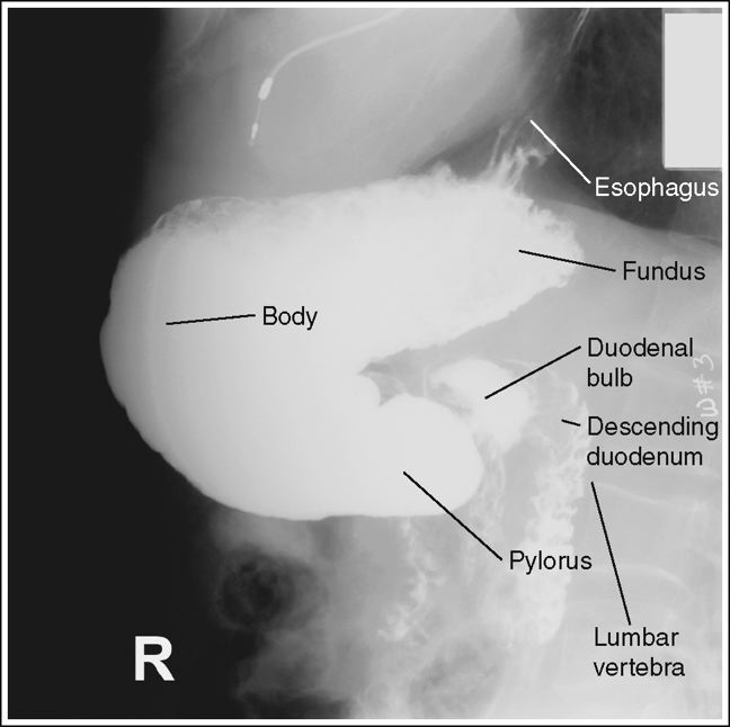

Lateral Stomach and Duodenum (CR and positioning)

Recumbent Right Lateral - Visualized the right retro-gastric space, duodenal loop and the duodenaljejunal junction

Upright left lateral - Visualized the left retro-gastric space

CR - At the level 1-2 inches above the lower rib margin (L1-L2) Center between the midcoronal plane and the anterior surface of the abdomen

Lateral stomach with proper positioning